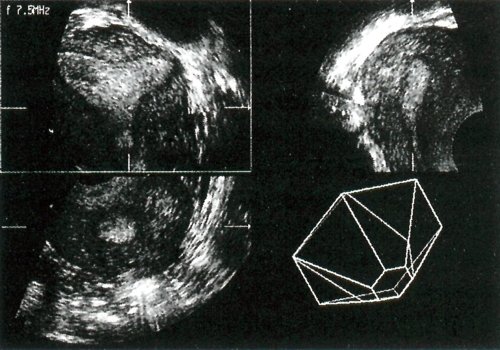

Полученное объемное изображение можно проанализировать сразу или сохранить для последующего изучения. Компьютер может переформатировать изображение в плоскостные срезы, которые напоминают картину, получаемую при обычной двухмерной ультрасонографии в В-режиме. Вывод этих изображений на экран занимает небольшое время; это самый простой способ просмотра трехмерных данных. На экране одновременно показываются три взаимно перпендикулярные плоскости, что позволяет легче представить анатомию матки (рис. 1). Количество и ориентация переформатированных срезов не ограничены и можно получить такие срезы матки, которые невозможны при обычном УЗИ. Наиболее информативная плоскость - поперечный срез через всю длину матки от дна до шейки. Эта плоскость, перпендикулярная направлению распространения ультразвукового луча, не видна при обычном трансвагинальном сканировании.

Рис. 1. Исследование матки с использованием срезов, сгенерированных компьютером. Обычные продольный и поперечный срезы приведены в проекции справа вверху и слева внизу. Третья проекция (слева вверху) - фронтальный срез через матку, который трудно визуализировать при обычном сканировании.